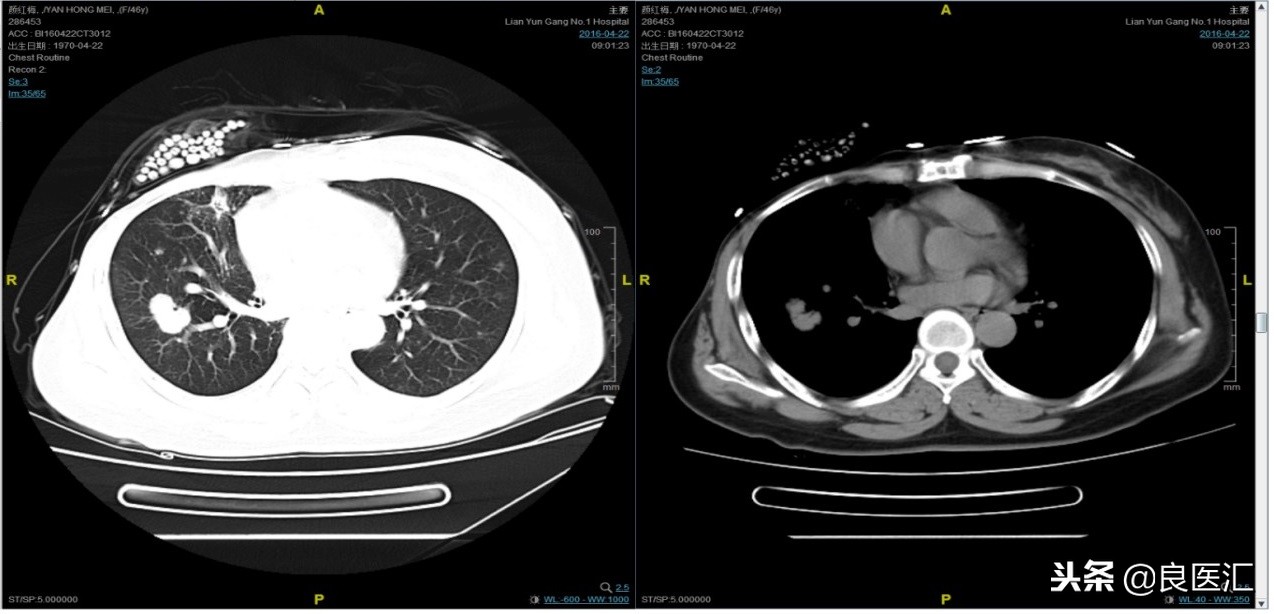

随访至2015年4月,患者肺部病灶复发。给予曲妥珠单抗+希罗达治疗(卡培他滨1500mg,一天两次口服)。 PFS1=17个月。

治疗期间2015-9-5复查CT如下: